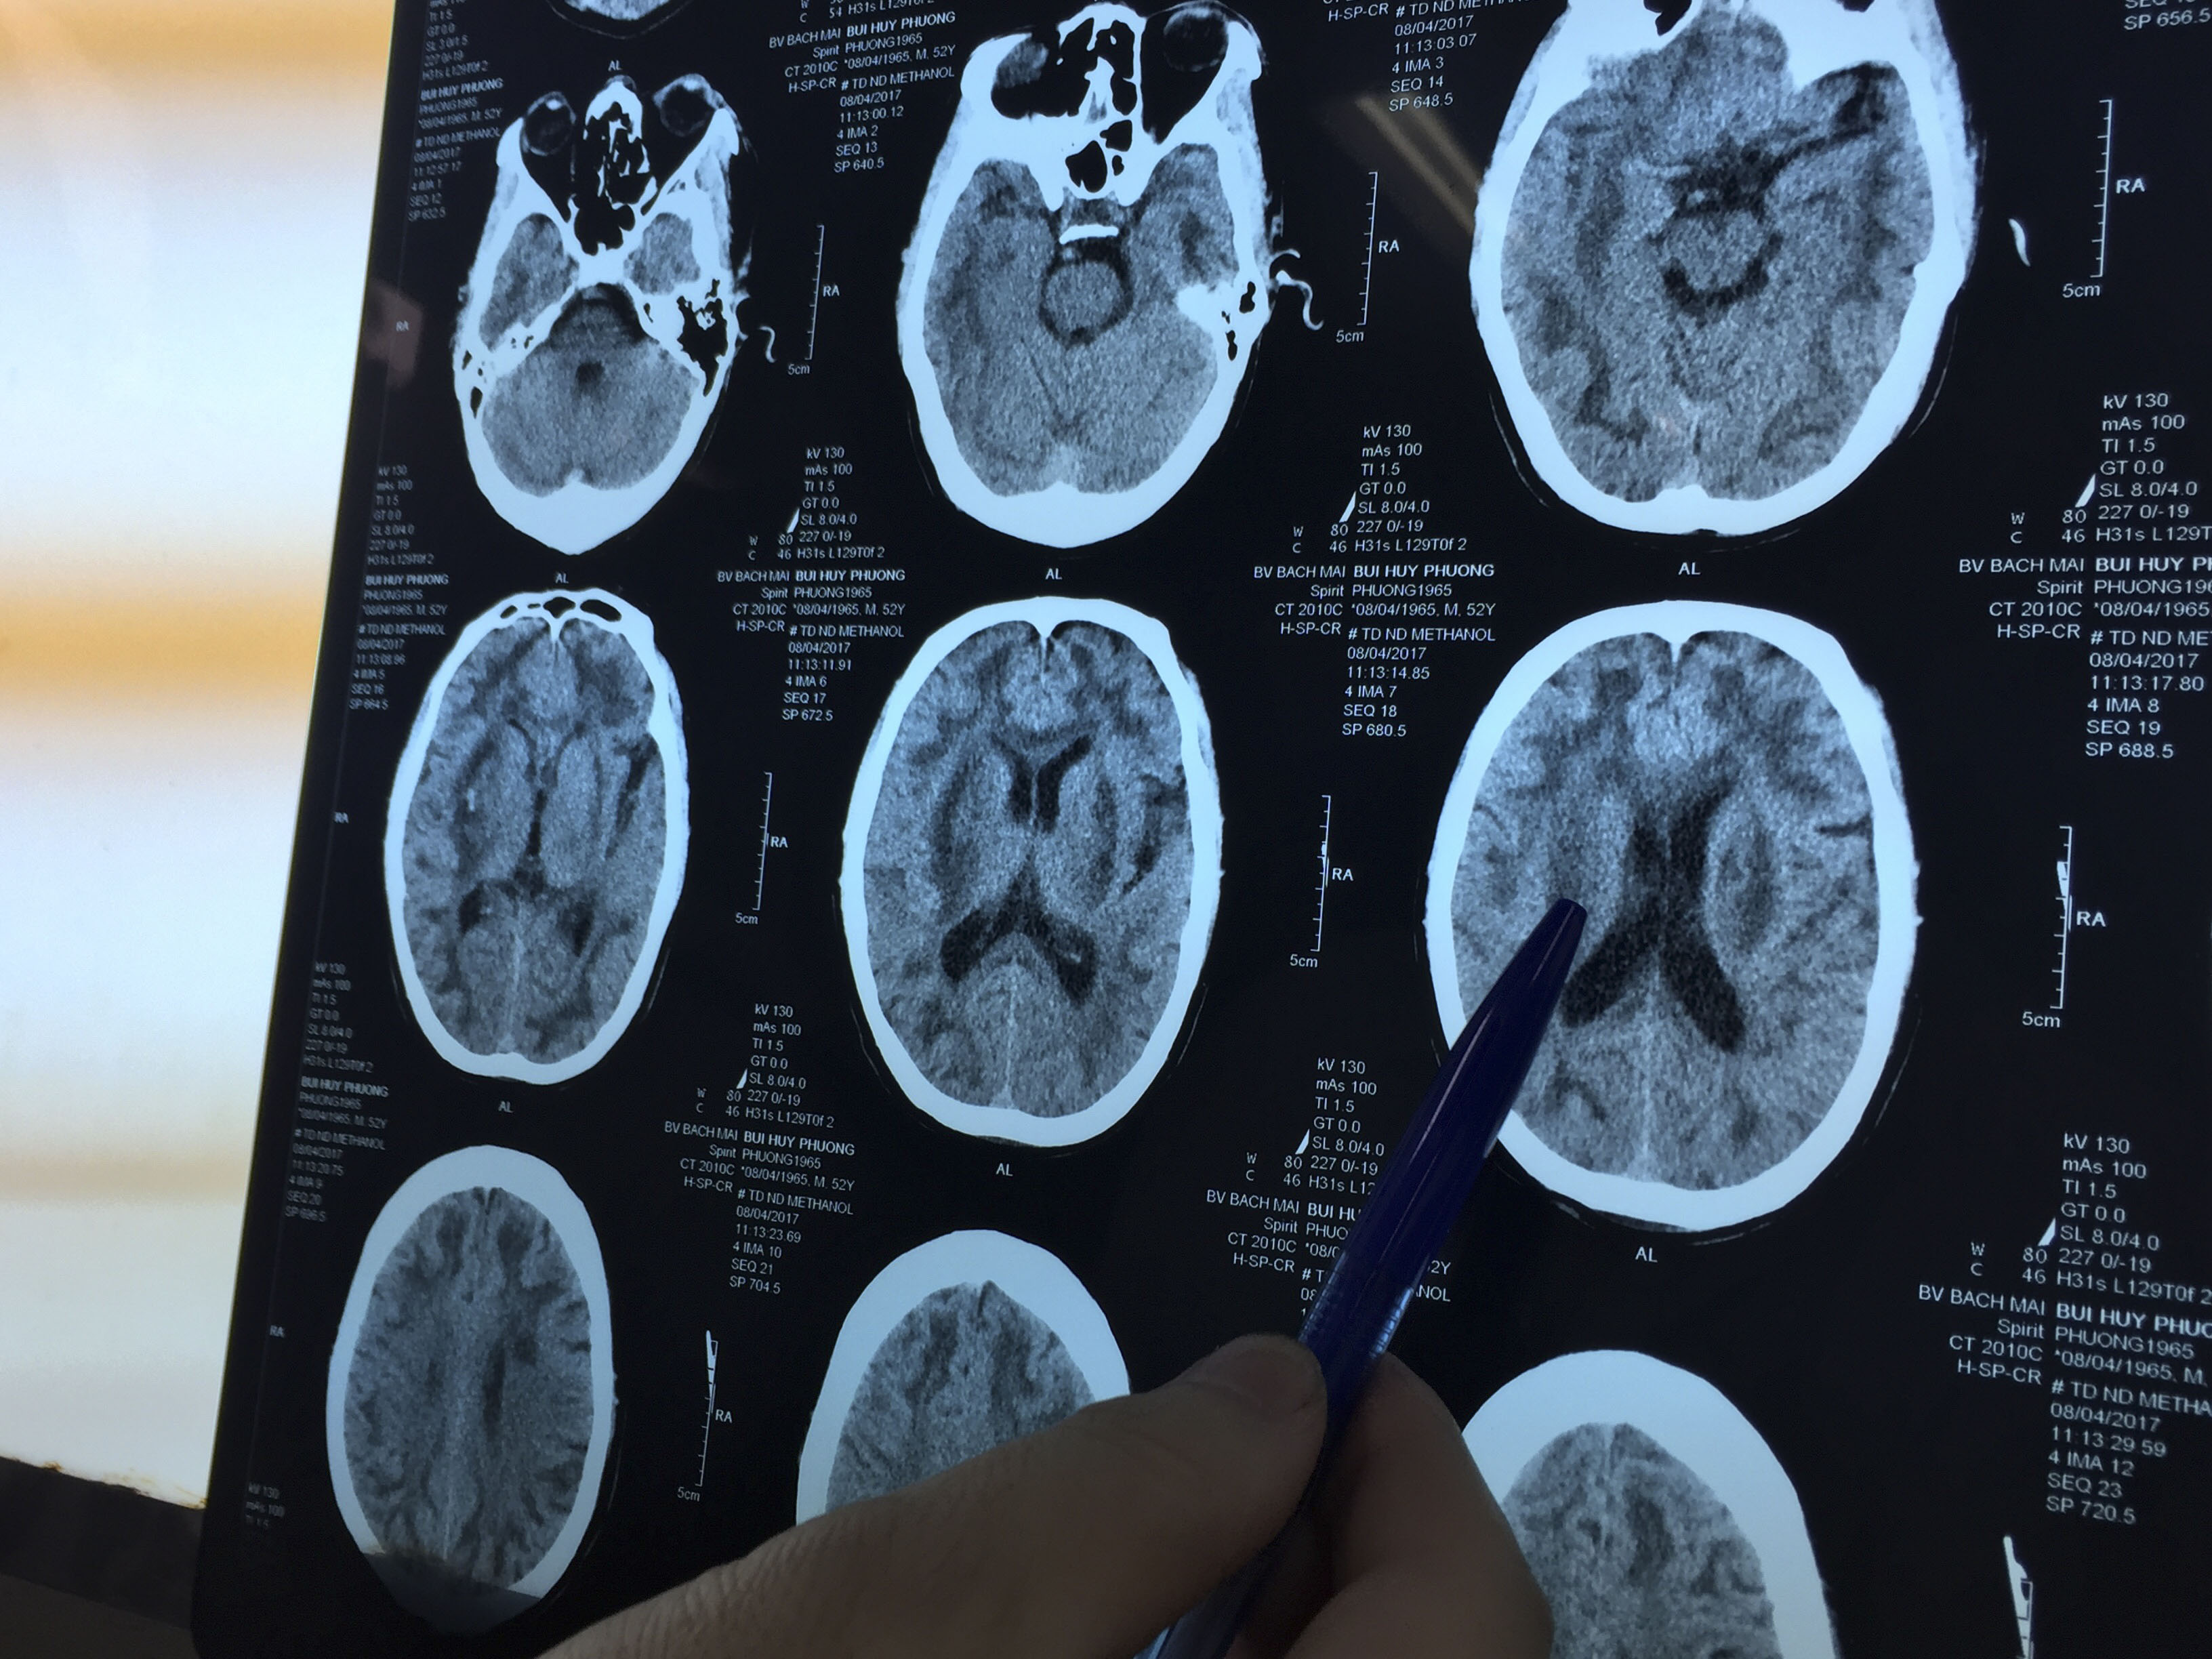

Theo thông tin từ TT Chống độc BVBM, đêm 6.4 đã tiếp nhận 1 BN nam B.H. P (SN 1965) ở Ngọc Khánh, Ba Đình – HN, sau 24h uống rượu ở 1 địa chỉ gần nhà và 1 địa chỉ ở Đê La Thành thì có dấu hiệu của ngộ độc. BN đến cấp cứu và được BV Giao thông vận tải chuyển đến trong tình trạng hôn mê, toan chuyển hoá. XN thấy nồng độ Methanol trong máu lên đến 45,9 mg/dl. BN đã được các thầy thuốc của TTCĐ điều trị bằng tất cả các liệu pháp tích cực đối với 1 tình trạng ngộ độc Methanol: lọc máu, hồi sức, thải độc… Đến 16h00 hôm nay (8.4), xét nghiệm Methanol trong máu đã âm tính nhưng đáng buồn là BN vẫn trong tình trạng hôn mê sâu, tổn thương não nặng nề: hình ảnh tổn thương chất trắng, nhân xám, thể trai đối xứng điển hình do ngộ độc Methanol kèm theo ổ xuất huyết bao ngoài phải, nguy cơ di chứng và tử vong rất cao.

IMG 0784